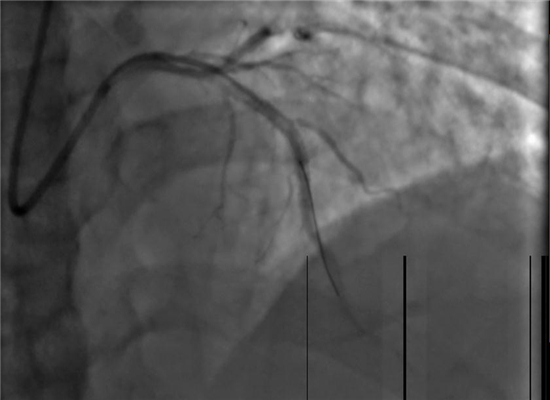

急诊PCI手术

在向患者家属详细说明手术的必要性及风险并征得同意后,杨勇主任带领科室介入手术团队迅速展开工作,将患者送入了导管室,并以最快的速度完善术前准备。23:02分开始手术,介入团队密切配合,快速穿刺桡动脉、置管、造影、开通闭塞血管,植入支架。经过约40分钟的全力救治,成功挽救了患者的生命。目前,术后患者症状明显改善,恢复较好。

手术之前

手术之后